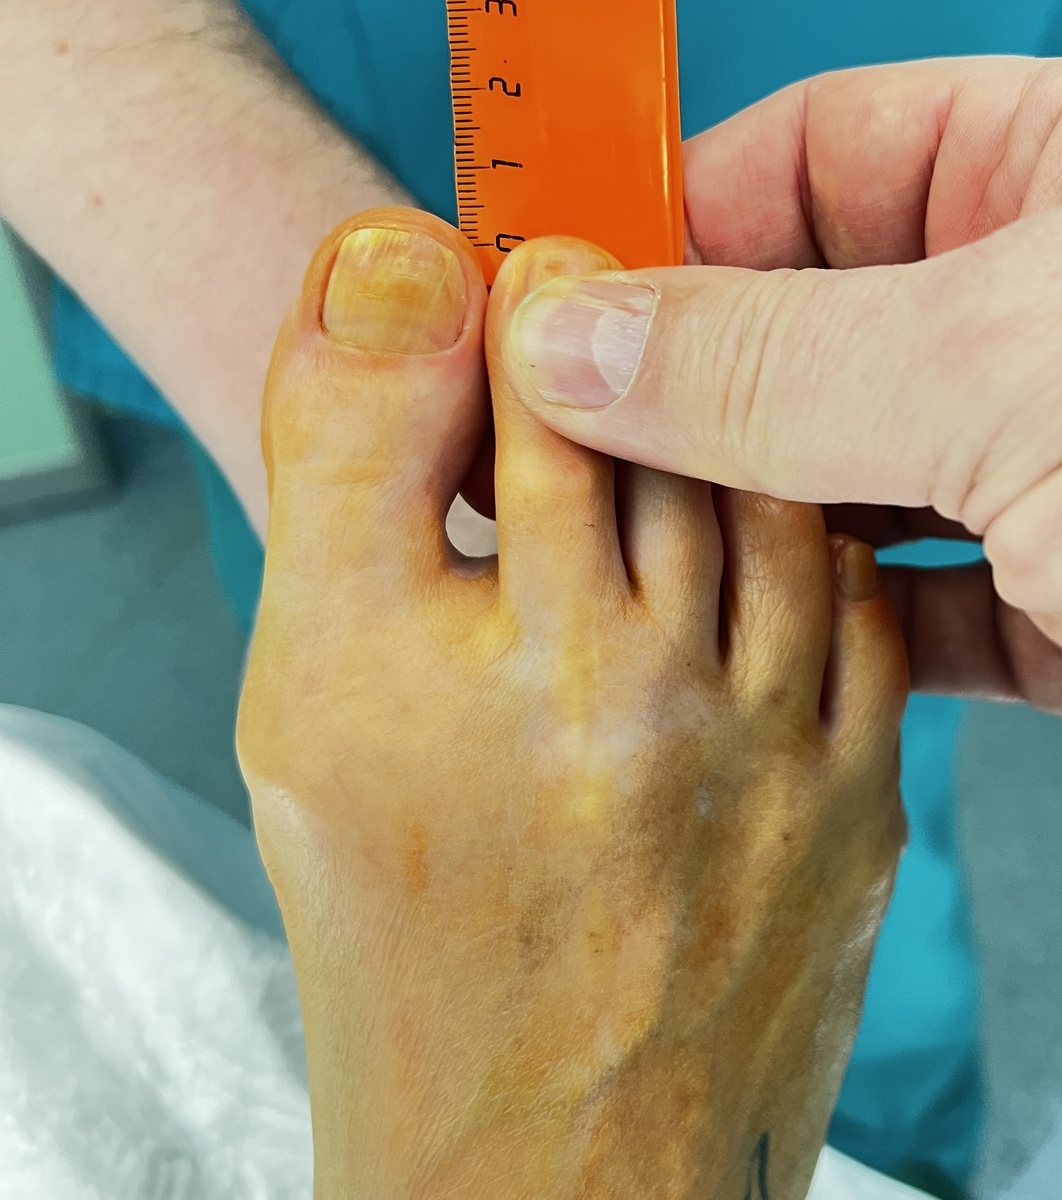

На фото первый палец не кажется уж очень длинным, но на самом деле (если его еще и распрямить) лишнего здесь много. Справа стопа сразу после операции - почувствуйте разницу.